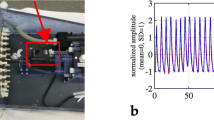

Phantom and motion tables

The National Electrical Manufacturers Association (NEMA) 2001 International Electrotechnical Commission (IEC) phantom (Data Spectrum Corp., Hillsborough, NC) consisting of a quasicylindrical cavity (280 × 210 × 180 mm) and six spheres (Model ECT/IEC -BODY/P) was used for this study. The spheres were 10, 13, 17, 22, 28, and 37 mm in diameter, and their wall thickness was 1 mm. All of the spheres were filled with 18F solution of 36.7 kBq/mL, and the background was filled with air. The radioactivity was equal to SUV = 15. A newly designed motion system was used in this study to simulate respiratory motion. The NEMA phantom was placed on a moving table, and a motor-driven table oscillated with a displacement of 2 cm in the craniocaudal direction and a frequency of 15/min. The parameters were selected to simulate displacements and respiratory cycles typically observed in normal respiratory motion.

The motion tracking was recorded by a real-time position management (RPM) respiratory gating system (Varian Medical Systems, Palo Alto, CA). The motion was sinusoidal. A trigger was set at a defined phase within the respiratory cycle and initiated the acquisition cycle in gated PET and dynamic CT. Finally, the respiratory cycles were divided into eight phases.

The %counts of the gPET–HCT and the gPET–4DCT in each respiratory phase are shown in Fig. 2. In gPET–HCT, the %counts of the central phases (phases 2, 3, 6, and 7) were smaller than those of edge phases (phases 1, 4, 5, and 8). The sphere position during the HCT scan was the midpoint between phases 2 and 3. On the other hand, the %counts of edge phases (phases 1, 4, 5, and 8) were smaller than those of central phases (phases 2, 3, 6, and 7). Figure 3 shows the gated PET and CT images in each respiratory phase. In the gPET–HCT images, the distribution of radioactivity was not homogeneous. The hot area was located in the center position of the respiratory movement where the sphere was placed during HCT scanning. In gPET–4DCT, the distribution of radioactivity was homogeneous.